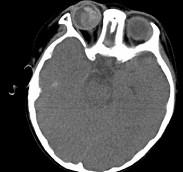

问题 男,2岁、右眼白瞳症1个月,CT影像如图,最可能的诊断为()

选项 A.眼球内寄生虫病 B.永存原始玻璃体增生症 C.脉络膜骨病 D.Coats病 E.视网膜母细胞瘤

答案 E